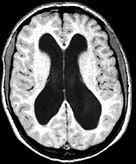

Klar erkennbar sind die mit Flüssigkeit gefüllten Ventrikel (schwarze Fläche).

Normalerweise weißt die Gehirnrinde eine Dicke von etwa 4 Zentimetern auf, bei ihm war sie jedoch auf die Dicke eines Papierblattes zusammengeschrumpft. Lorber schätzte, dass das gesamte Gehirn des Mannes nur etwa 100 Gramm wog. Ein normales Gehirn eines Erwachsenen wiegt zum Vergleich etwa 1,3 Kilogramm, also 13 mal soviel. Der Student litt unter einem Wasserkopf, einer Krankheit, bei der die Gehirn-Rückenmark-Flüssigkeit anstatt um das Gehirn zu zirkulieren und anschließend in den Blutstrom überzugehen, im Inneren aufgestaut wird.